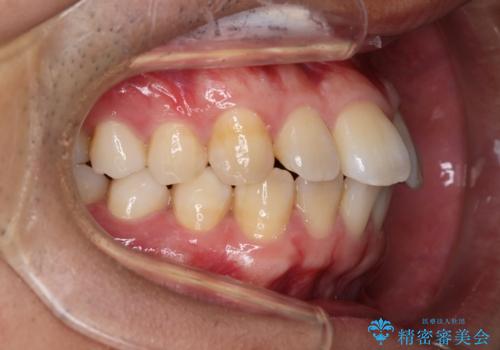

上の前歯が出ているという主訴が綺麗に改善されました。

その他の部位のがたつき、奥歯の噛み合わせも以前と比べると良くなっています。

目立たない装置で治療期間も10ヶ月と短く終了することができました。